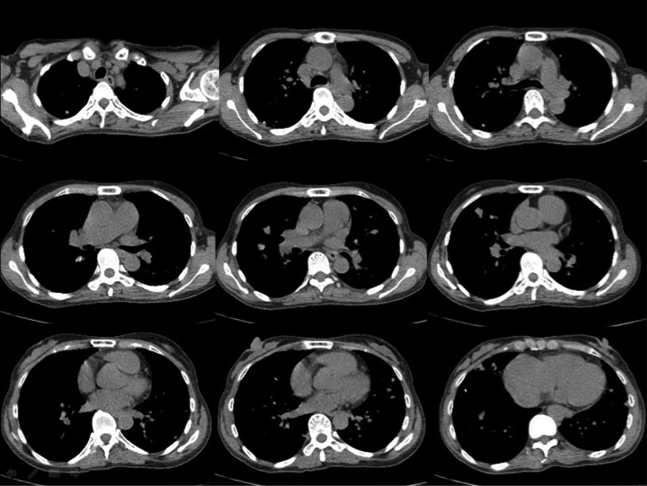

A 56 year old housewife, who was a non-smoker and non-drinker, presented with dry cough for three months. She denied other complaint and she enjoyed a good past health. Her physical examination was unremarkable. Her chest X-ray (CXR) showed patchy infiltrates in bilateral lower zones and several lung nodules bilaterally (Fig 1). Her initial blood tests including complete blood picture, renal & liver function test, erythrocyte sedimentation rate, urate, lactate dehydrogenase and tumor markers (including carcinoembryonic antigen, alpha-fetoprotein, CA 15.3, CA 19.9 and CA 125) were normal. Her sputum was negative for culture, acid fast bacilli and cytology. Her urine routine microscopy was also normal. Contrast computer tomography (CT) thorax showed bilateral lung nodules with size 0.5-2cm, bilateral thin walled lung cysts with size 0.5-2.5cm and sub-segmental collapse of right middle lobe. Some of the nodules had speckles of calcifications inside (Fig 2A, 2B). Fibre-optic bronchoscopy and transbronchial biopsy (FOB+TBBx) were not diagnostic. We had discussed with her about different investigation options included positron emission tomography (PET)-CT and repeating biopsy by FOB+TBBx under fluoroscopy guidance or CT guided fine needle aspiration (FNA). She opted for PET-CT. Her PET-CT was reported as “There were multiple hyper-metabolic nodules (maximum standardized uptake value (SUVmax ) 4.4). They were suspicious of metastases.” There were also multiple hypo-metabolic lucent cystic lesions scattered on both lungs. A complex cystic mass with calcification and some F-18 fluorodeoxyglucose (FDG) avidity was found incidentally at the right adnexal region (Fig 3A, 3B). At that juncture, the working diagnosis was gynaecological malignancy with multiple lung metastases. FOB+TBBx repeated under fluoroscopy guidance showed nodular deposition of extracellular amorphous eosinophilic material in the alveolar spaces. These depositions were salmon pink in Congo red section, and they showed yellow-green birefringence in polarized microscopy. The histological feature was compatible with amyloid. Total abdominal hysterectomy and bilateral salpingo-oophorectomy was done by the gynaecologist and the right adnexal lesion was found to be a mature ovarian teratoma with thyroid tissue. Thus the right ovarian teratoma was just an incidental finding and was not related to the amyloidosis. Further assessment and workup were done to look for possible condition that was known to be associated with amyloidosis such as chronic inflammatory diseases and monoclonal plasma cell dyscrasias. Further enquiry revealed she had chronic dry mouth for over 10 years. Her antinuclear antibody (ANA) titer was raised (1/640) and her anti-Ro (SS-A) titer was positive. Her schirmer test was 0mm over both eyes, indicating severe dry eye. Although the histology of her salivary gland biopsy was reported as within normal limit, she was considered as a case of primary Sjogren’s syndrome by the rheumatologist and symptomatic treatment was provided. Clinically, no other organ was involved by the amyloidosis. Thus the final diagnosis was nodulocystic pulmonary amyloidosis associated with primary Sjogren’s syndrome. An interval CT thorax about two years later showed no significant interval change.

Figure 2a

Figure 2b